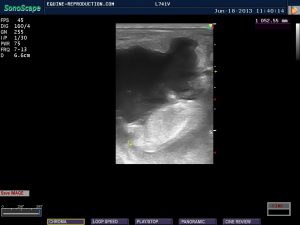

By day 26, the newly emerging allantoic sac can often be seen below the embryo proper – a process started somewhere around 22-24 days. This will increase in size, while the yolk sac (which is above the embryo) will decrease in size resulting in an apparent “floating upwards” of the embryo within the vesicle. It is worth comparing this 26 day image with the 27 day image immediately below it, where one can see a dramatic difference in the size of the allantoic sac. This difference may be as a result of different rates of progression in different mares, as well as transducer angle. It is worth while remembering that while there are averages, there are no absolute standards!

The comparison in size of the allantoic sac (lower) and yolk sac (upper) is clearly visible, with the former increasing in size causing the embryo to appear to “rise” in position.